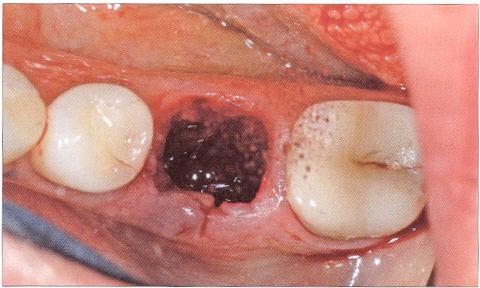

Воспаление альвеолярной части десны или альвеолит как раз и является воспалительным процессом, развивающимся в лунке зуба. После того как зуб удален, на его мете образуется лунка, покрытая сгустком, который при наличии инфекционного процесса уплотняется, на месте лунки возникает нагноение.

Основной причиной развития воспалительного поражения в лунке вырванного зуба считается присутствие очага инфекции в ротовой полости. В качестве очага инфекции могут выступать кариозные зубы, а также бактериальная инфекция.

Устранить альвеолит можно при помощи промываний пораженной области антисептиками, аппликаций и компрессов с противовоспалительными и противоотечными препаратами, убивающими патогенные микроорганизмы и оказывающими заживляющее действие.

Альвеолит — воспаление в лунке удаленного зуба. Основный признак — затянувшееся заживление лунки, отсутствие кровяного сгустка, сильная боль в лунке зуба. Другие симптомы — увеличение подчелюстных лимфоузлов, неприятный запах изо рта, слабость, недомогание, температура тела до 38°С.